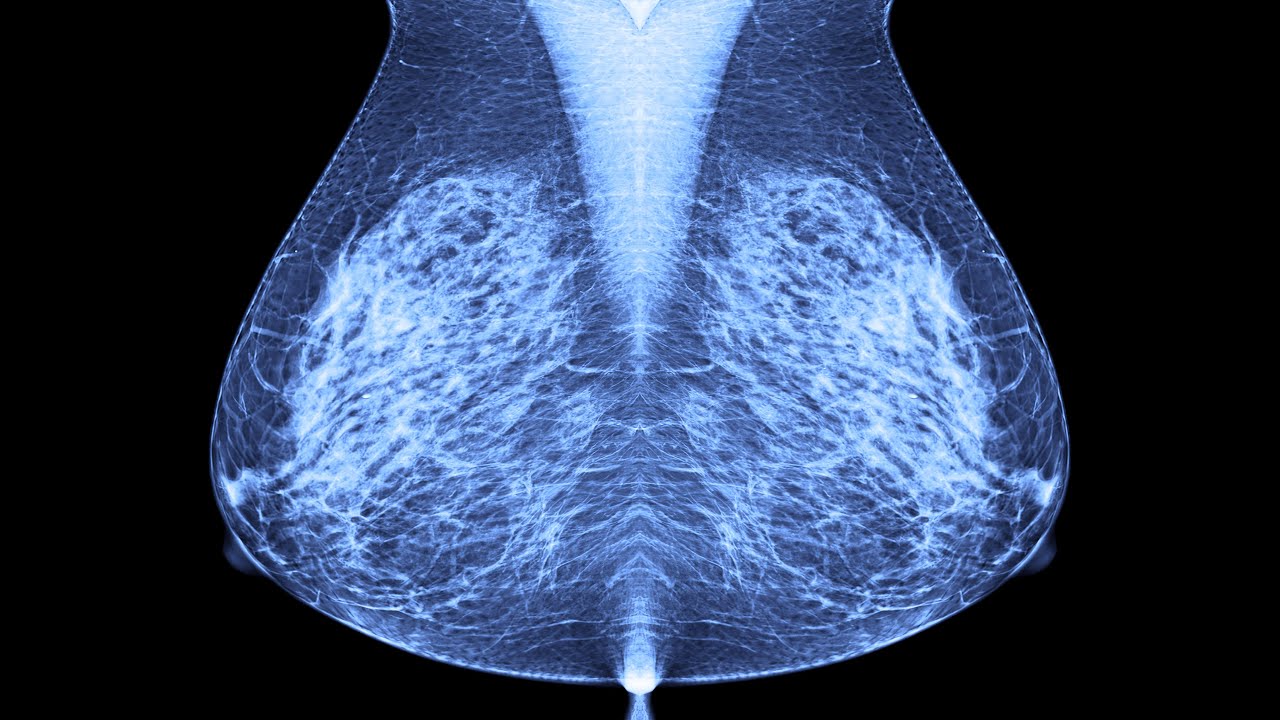

começa a ter uma uma uma nuvem com sua cima do vídeo mosquito assim veio e todos eles se agarra e colam naquela bactéria naquele vírus ou naquele a gente que tá no sangue e aí a gente consegue bloquear e pedir que esse micróbio que esse l faça algum mal para o nosso corpo é mas para isso a gente vai ter uma gama de mundo globulinas normalmente a gente se preocupa com aí gegê e com a mgm aí gegê é uma hemoglobina bem pequena vocês podem ver aqui a fotinha dela ela ela vai ter um formato